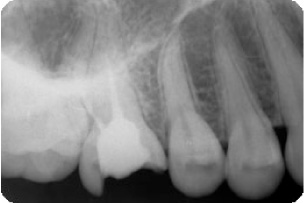

矢印の付近、黒い部分が 病気で骨が溶けています。

黒い病気の部分が消えています。